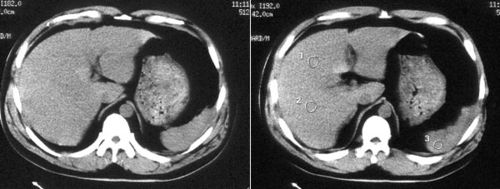

五,肝破裂出血

ct诊断:高度怀疑肝左内叶肝破裂. 手术

肝破裂ct图片

肝破裂ct影像表现

肝破裂ct影像表现图片

肝脏破裂出血ct图片